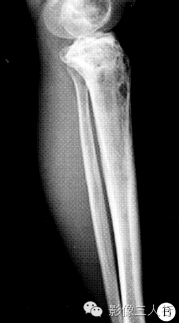

【病例】左胫骨弥漫性非霍奇金淋巴瘤1例X线MR影像表现

影像诊断:尤因肉瘤可能大,低毒菌感染待排。

PLB较特征的影像表现可概括为:①早期肿瘤仅在骨髓腔内生长,外形保持正常,此时在X线上可表现正常,或仅表现为病变骨质内斑点状的溶骨性低密度,随着肿瘤组织向骨内膜生长,浸润、侵入到骨皮质内,使病变骨呈膨胀性改变,骨皮质呈“筛孔”或“鼠咬”状溶骨性破坏,破坏区边缘不清楚。②肿瘤的MR信号强度与肿瘤内部的组织成分有关。瘤细胞密度高、纤维成分多时,其T1、T2信号强度都相对较低。③骨膜反应较轻微。偶见的骨膜反应为单层型、板层型和针刺状,这种类型的骨膜反应在其他类 型骨原发恶性肿瘤中很少见到。④PLB的增强后MRI常为较均匀的中等或明显强化。⑤PLB的软组织肿块多以病变骨质为中心性,呈包绕性生长。